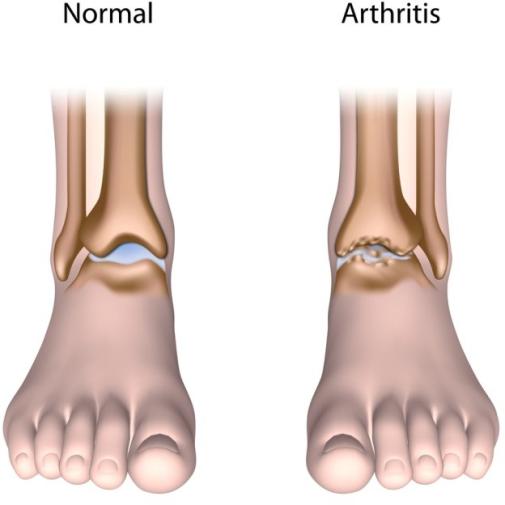

Artritis je općeniti naziv za grupu bolesti koja obuhvaća više od 100 bolesti. Osteoartritis označava upalu zgloba koja nastaje uslijed degenerativnih promjena struktura koje čine zglob ( hrskavica + kosti ). Pored toliko vrsta artritisa nije ni čudno da se zglobovi tijekom vremena troše zajedno sa hrskavicom koja ima funkciju ” jastuka ” odnosno ublažavanja udaraca i trenja između zglobnih površina. Osim hrskavice i posljedičnog oštećenja koštanih struktura okolno meko tkivo ( ligamenti, tetive, sluzne vreće …) se također s vremenom troši. Sve to će dovesti do stanja da se zglob više ne može gibati u normalnom fiziološkom opsegu pokreta

OA skočnog zgloba ( slika 13. i 14. ) je bolno stanje koje otežava aktivnosti svakodnevnog života, u prvom redu hodanje. Skočni zglobovi su strukture koje ljudskom tijelu omogućavanju hodanje, trčanje i skakanje

Površine tih kostiju su prekrivene hrskavicom, a to mekano tkivo ima svrhu zaštite kostiju i ublažavanja udaraca. Osteoartritis uzrokuje trošenje hrskavice tijekom vremena što dovodi do trenja kost o kost i stvaranja koštanih izdanaka sa posljedičnom boli, oticanjem i gubitkom funkcije skočnog zgloba